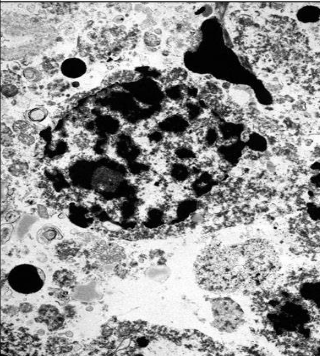

kas būdinga nekrozei - negrįžtamiems pažeidimams (ląstelės morfologija)

branduolio chromatino negrižt. pakitimai

membranos fragmentacija

formuojasi meilininės figūros

ET degradacija

pabrinkimas

kokie yra branduolio nykimo būdai

kariopiknozė

karioreksė

kariolizė

kas vyksta kariopiknozės metu

chromatinas sutrūkinėja ir tankėja, nyksta be pėdsako

kas vyksta karioreksės metu

branduolio chromatinas fragmentuojasi

(dažosi juoda spalva)

kas vyksta kariolizės metu

branduolio chromatinas tirpsta

susdiaro blyškios ertmės